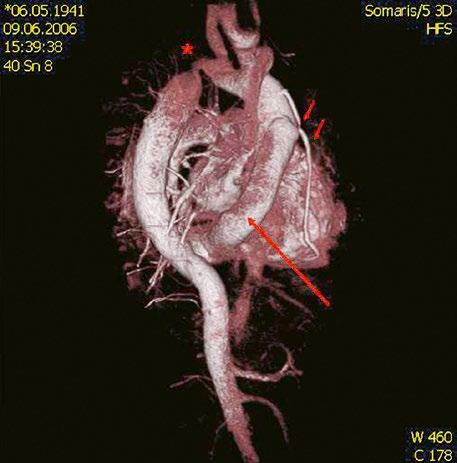

Obr. 45.11 CT angiografie, defekt typu sinus venosus superior je označen hvězdičkou, anomální pravá horní plicní žíla ústící do horní duté žíly je označena šipkou

PS – pravá síň, LS – levá síň

Obr. 45.12 CT angiografie s 3D rekonstrukcí u pacientky s defektem typu sinus venosus superior a s parciálním anomálním návratem dvou pravostranných plicních žil z horního a středního laloku do horní duté žíly, pravá dolní plicní žíla ústí normálně do levé síně